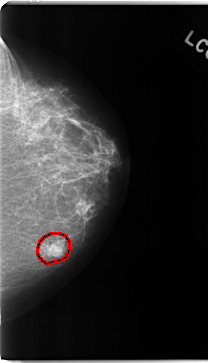

C_0161_1.LEFT_MLO

LEFT_MLO LINES 4752 PIXELS_PER_LINE 2840 BITS_PER_PIXEL 12 RESOLUTION 50 OVERLAY

FILE: C_0161_1.LEFT_MLO.OVERLAY

TOTAL_ABNORMALITIES 1

ABNORMALITY 1

LESION_TYPE MASS SHAPE LOBULATED MARGINS MICROLOBULATED

ASSESSMENT 5

SUBTLETY 5

PATHOLOGY MALIGNANT

TOTAL_OUTLINES 1

BOUNDARY